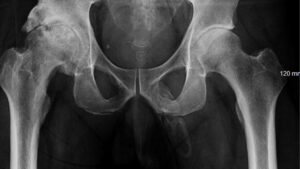

diverse Dilema de diagnostic: penisul unui bărbat se transforma în os 18 decembrie 2024 by Echipa Club S&T | Leave a Comment Razele X au dezvăluit „calcificare extinsă, asemănătoare plăcii” de-a lungul lungimii penisului unui bărbat. (Credit imagine: Georges El Hasbani, et al./Urology Case Reports, CC BY NC-ND 4.0) Simptomele: Pacientul a avut dureri la genunchi după ce a căzut pe fese, determinându-l să caute tratament la camera de urgență. În timpul unei examinări, bărbatul a descris […] Read more »